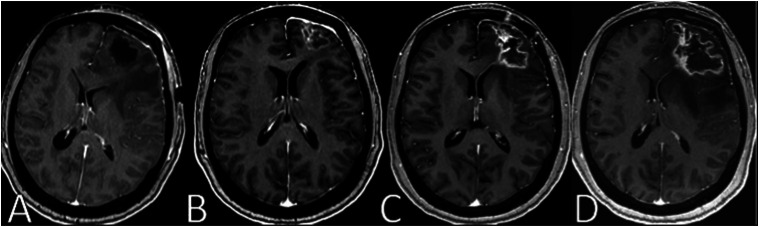

Case reports: Case 1 discusses a 41-year-old male with GBM, highlighting the challenges of differentiating tumor progression from treatment-induced pseudoprogression. Case 2 discusses a 45-year-old female with brain metastatic malignant melanoma, presenting radiological evidence of progressive disease while undergoing nivolumab treatment. Case 3 discusses a 37-year-old male with GBM, where radiological evidence indicates progressive disease while receiving pembrolizumab treatment.

Management and outcomes: In case 1, we discussed the challenges of distinguishing true tumor progression from treatment-induced pseudoprogression, leading to the continuation of the same treatment due to pseudoprogression. In case 2, post-surgery pathology revealed radionecrosis and treatment-related changes, guiding the continuation of nivolumab therapy. Case 3 involved a pathologically confirmed progression, and the patient received best supportive care due to his performance status.